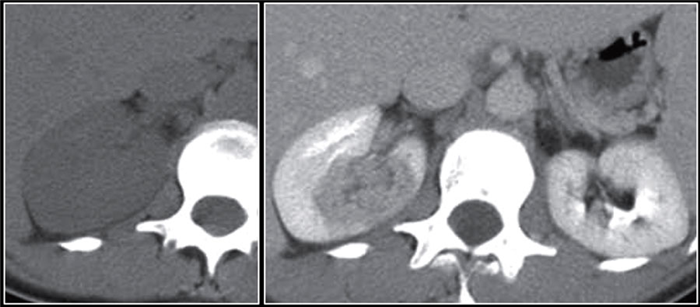

(Слева) КТ правой почки с контрастированием, аксиальная проекция: выявлено крупное образование в почке, не накапливающее контраст и окруженное капсулой с плотностью 20 HU (предположительно абсцесс).

(Справа) УЗИ правой почки в сагиттальной плоскости: у того же пациента выявлено округлое анэхогенное образование с низкоуровневыми внутренними эхо-сигналами и задним акустическим усилением. Лихорадка в анамнезе и данные визуализации указывают на наличие абсцесса.